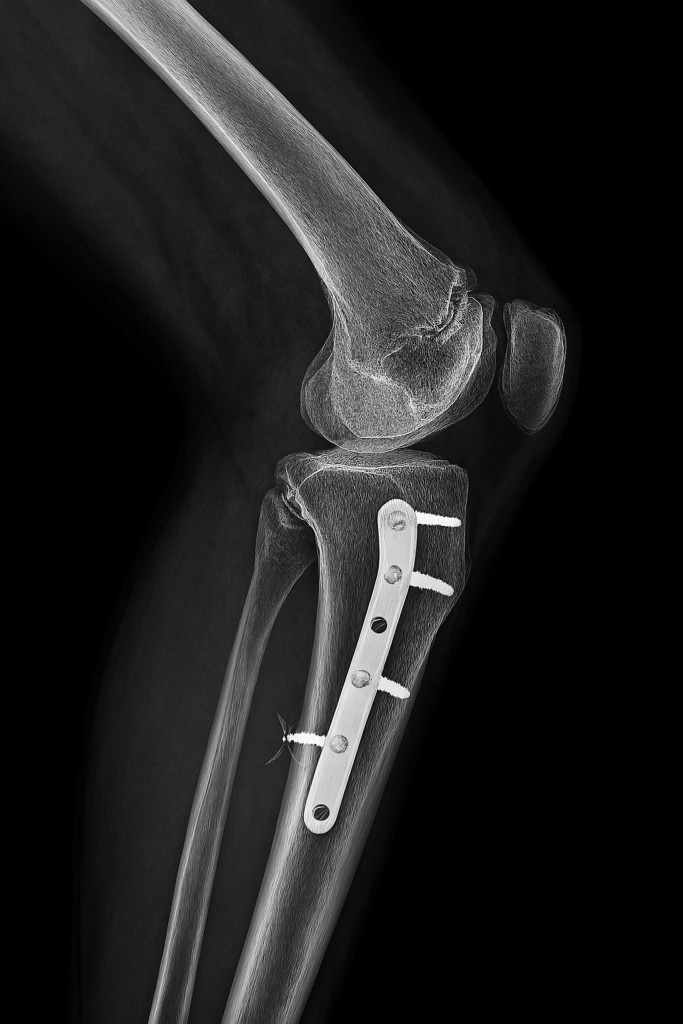

Athletic movement involves high-load, high-velocity actions that place extreme stress on joints, muscles, and connective tissues. Sprinting, jumping, pivoting, and tackling all generate forces that exceed normal physiological thresholds. Ligaments such as the anterior cruciate are particularly vulnerable in sports requiring rapid deceleration and directional change. Muscle strains often result from eccentric contractions – where the muscle lengthens while under tension, creating microscopic damage. Tendons can degenerate over time due to repetitive loading – leading to chronic conditions like tendinopathy. Bone stress injuries emerge when cumulative force exceeds the bone’s ability to remodel – often seen in long-distance runners. The kinetic chain – the interconnected system of joints and muscles – can fail when one segment compensates for another, increasing injury risk. Poor biomechanics, even in elite athletes, can amplify vulnerability. Injury is not just a failure of tissue – it’s a signal of systemic overload and imbalance.

The Role of Elite Medical Support

Professional athletes have access to multidisciplinary medical teams that optimize every phase of recovery. Sports physicians, physiotherapists, orthopedic surgeons, and nutritionists collaborate to create individualized treatment plans. Diagnostic imaging such as MRI and ultrasound allows precise identification of tissue damage – guiding targeted interventions. Surgical techniques are often minimally invasive – reducing recovery time and preserving function. Rehabilitation protocols are progressive and evidence-based – incorporating strength, mobility, proprioception, and sport-specific drills. Manual therapy, dry needling, and neuromuscular re-education accelerate tissue remodeling. Nutrition is tailored to support healing – with emphasis on protein synthesis, anti-inflammatory compounds, and micronutrient balance. Recovery is monitored through biomarkers, performance metrics, and subjective feedback. This level of care is rarely available to the general public – creating a disparity in recovery outcomes.